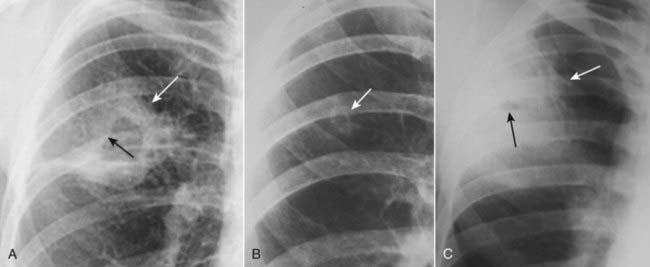

Figure 12-4 Mediastinal adenopathy from Hodgkin disease.

Lymphadenopathy frequently presents with a lobulated or polycyclic border due to the conglomeration of enlarged nodes that produce the mass (solid white arrows). This finding may help differentiate lymphadenopathy from other mediastinal masses. Mediastinal lymphadenopathy in Hodgkin disease is usually bilateral (dotted white arrows) and frequently asymmetric.

image Mediastinal lymphadenopathy in Hodgkin disease is usually bilateral and asymmetrical (Fig. 12-4). In addition, asymmetrical hilar adenopathy is associated with mediastinal adenopathy in many patients with Hodgkin disease.

image Unlike teratomas and thymomas, which are presumed to expand outward from a single abnormal cell, lymphomatous masses are frequently composed of several contiguously enlarged lymph nodes. As such, lymphadenopathy frequently presents with a border that is lobulated or polycyclic in contour owing to the conglomeration of enlarged nodes that make up the mass.

imageOn chest radiographs, this finding may help differentiate lymphadenopathy from other mediastinal masses.